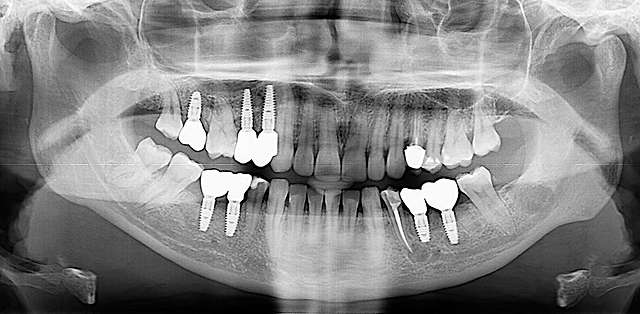

Surgical guides are used for more safety and precision in complex cases that require dental implant therapy. Guides are 3D printed based on the digital planning of the surgery, using specialised software and the CBCT of the patient.

For optimal esthetic results, the final design must always be the refference for the surgery. This design together with the CBCT of the patient are compiled to find the ideal position of the dental implants.